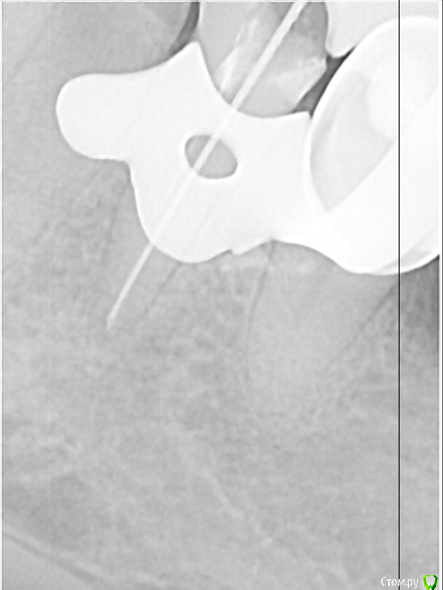

Всем доброго дня! В коем то веке появилась свободная минутка и решил поделиться с вами несколькими кейсами. Обострение хронического периодонтита 27, каналонаполнитель в нёбном канале. Коффердам, извлечение каналонаполнителя, хлорка, лимонка, УЗ, кальций. Обтурация Ah+ латеральная компакция.